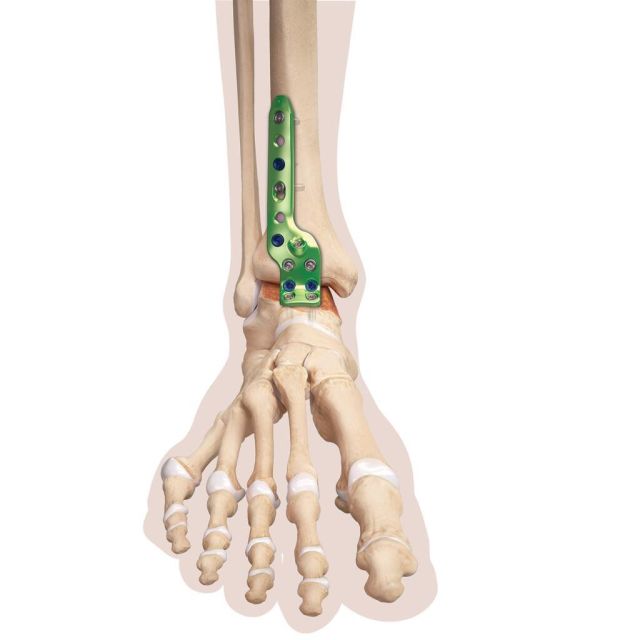

Ist die Knochenqualität schlecht, kann die Stabilisierung mittels winkelstabiler Plattensysteme vorgenommen werden.

Um das Weichteilrisiko möglichst gering zu halten, kann die Operation in arthroskopischer Technik vorgenommen werden). Dies reduziert den postoperativen Heilungsverlauf, benötigt aber ein hohes Maß an chirurgischer Erfahrung. Für diese Technik sind spezielle kleine Plattensystem entwickelt worden, um eine zusätzliche Stabilisierung erreichen zu können, falls die Knochenqualität eine stabile Fixierung mittels zweier Schrauben nicht zulässt.